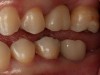

Fig 6. Clinical presentation of patient with a failing tooth No. 8.

Figure 6

Plugging into digital workflows provides opportunities to integrate CAD/CAM technologies at every step of the treatment process for dental implants. In another example, a patient presented with a failing tooth No. 8 (Figure 6 and Figure 7). After discussing treatment options, the patient chose to forgo any treatment to address tooth and soft-tissue asymmetries and wanted to proceed with a dental implant-supported restoration without additional treatment. After integrated 3-dimensional planning, the tooth was extracted, and then an implant and the final custom CAD/CAM abutment (titanium base with zirconia supra-structure) were placed with a provisional restoration in the same visit (Figure 8 and Figure 9). Soft-tissue grafting was also done at the same visit to address the deficient buccal tissue height on No. 8 (Figure 10). At 3 months, the patient presented for the final restoration, with excellent healing around the implant (Figure 11) and soft-tissue healing guided by the custom abutment (Figure 12).